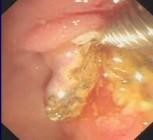

切开乳头

取出结石

【内镜下十二指肠乳头括约肌切开取石术(EST)】

胆总管结石可引起急性化脓性胆管炎和急性胰腺炎,一旦诱发重症胆管炎或重症胰腺炎,死亡率很高,因此,该病应及时尽早治疗。胆总管结石的治疗方式很多,但以不开刀方式通过内镜经口腔进行取石—EST是目前最好的治疗方法。